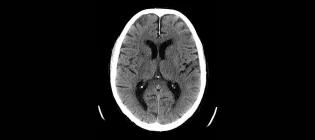

A CT scan of the brain, commonly used for patients with stroke

Senior Clinical Academic Fellow in Neuroradiology

I am interested in how we can improve imaging for patients with stroke.

Grant.Mair@ed.ac.uk